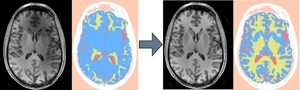

Many neuroanatomy studies rely on brain tissue segmentation in Magnetic Resonance images (MRI). The Expectation-Maximization (EM) theory offers a popular framework for this task. We studied the EM algorithm developed at the Surgical Planning Laboratory (SPL) at Harvard Medical School and implemented in the Slicer3 software. We observed that the segmentation lacks accuracy if the image exhibits some intensity inhomogeneity. Moreover the optimum parameters are challenging to estimate. This document aims at describing our solutions within the context of statistical modeling. Our contributions range from algorithm improvements to novel representations of the statistical distribution model. First we added a bias field correction module and exposed the most significant parameters. Second we proposed a new way to select the distribution of the tissues to be segmented. Finally we designed a set of interactive tools to make the segmentation process easier and more accurate. To validate the new segmentation pipeline, we performed our experiments on MRI data and a clinical expert evaluated our results. The source code developed for this work, i.e. the code of the MRIBiasFieldCorrection and EMSegment modules, is part of Slicer3 version 3.5 and can be downloaded by this command: svn co http://svn.slicer.org/Slicer3/trunk Slicer3